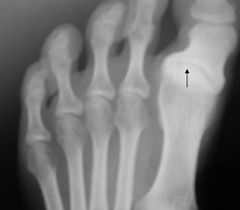

A right foot with hallux varus

Hallux varus is a deformity of the great toe joint where the hallux (great toe) is deviated medially (towards the midline of the body) away from the first metatarsal bone. The hallux usually moves in the transverse plane. Unlike hallux valgus, also known as hallux abducto valgus or bunion, hallux varus is uncommon in the West but it is common in cultures where the population remains unshod.